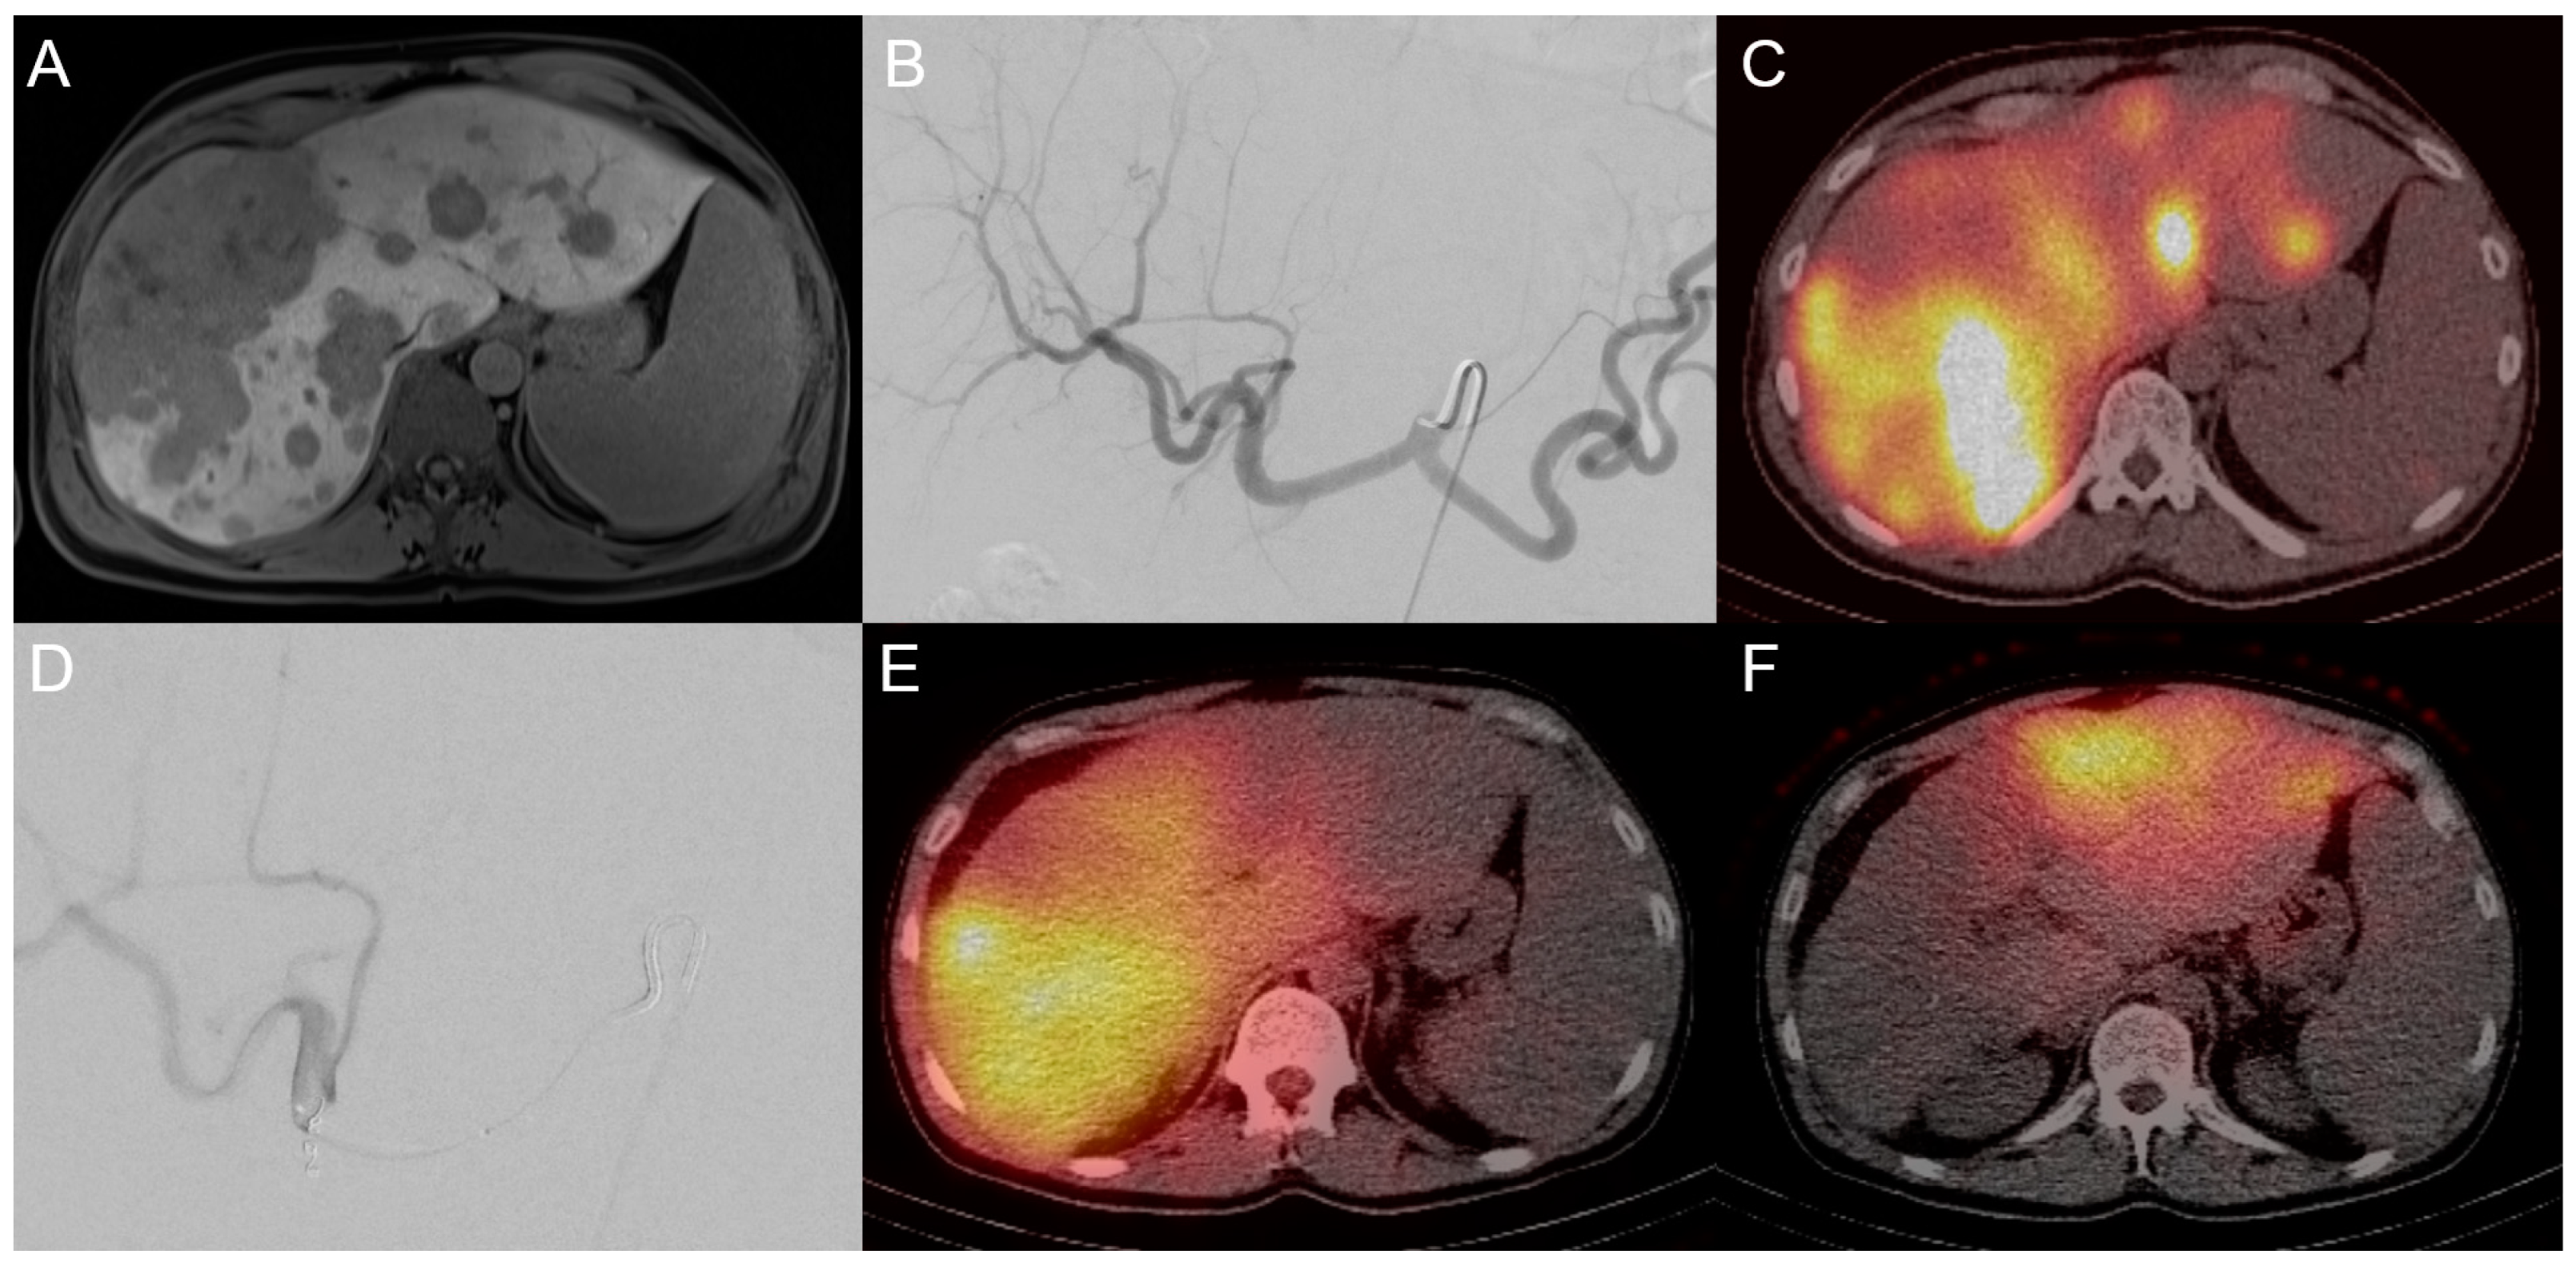

3.2. Transarterial Radioembolization (TARE)

4. Other Emerging Treatments